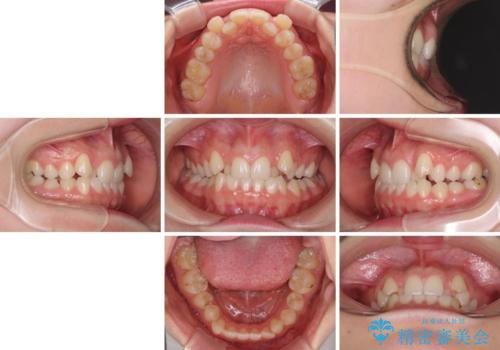

- 前歯のデコボコと八重歯を気にして来院された患者様です。

目立たない装置を希望されたので、上顎が裏側装置のハーフリンガルを選択し、左右上顎小臼歯1本ずつを抜歯して、矯正治療を行うこととしました。

治療期間の目安は2年半~3年間でしたが、予定通り治療が進み、2年半弱で終えることができました。

歯列はきれいに整い、治療期間も予定通りであり、患者様には大変満足していただきました。